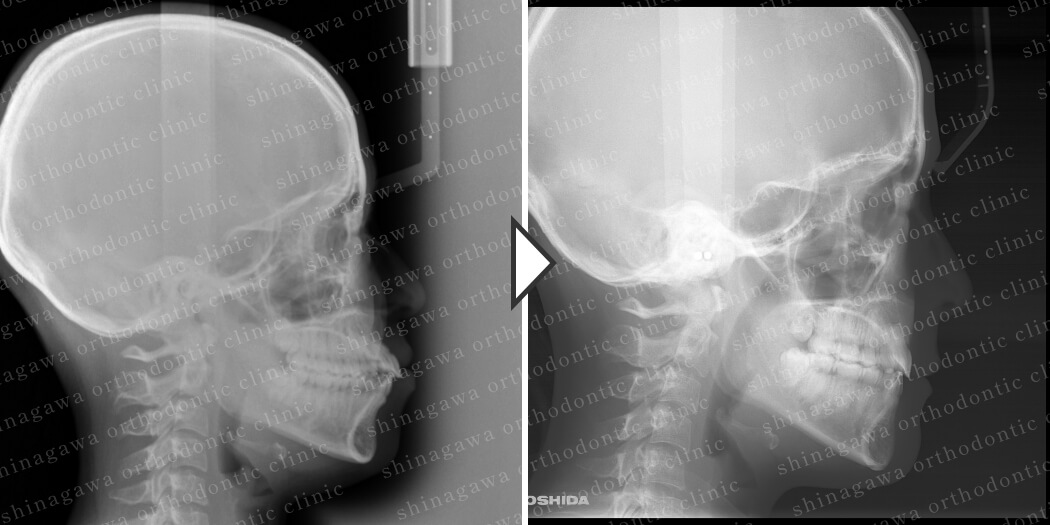

症例7

上下顎前突

| 年齢 | 25 歳 |

|---|---|

| 性別 | 女性 |

| 住所 | 神奈川県川崎市 |

| 主訴 | 出っ歯 |

| 不正咬合の種類(診断) | 上下顎前突 |

| 装置 | リンガル |

| 抜歯/非抜歯 | UR4, UL4, LR4, LL4 |

| 期間 | 32M |

| 費用 | 1,430,000 円 |

| リスク・副作用 | 矯正治療による歯の移動に伴う痛み, 虫歯, 歯肉退縮, 歯根吸収 |